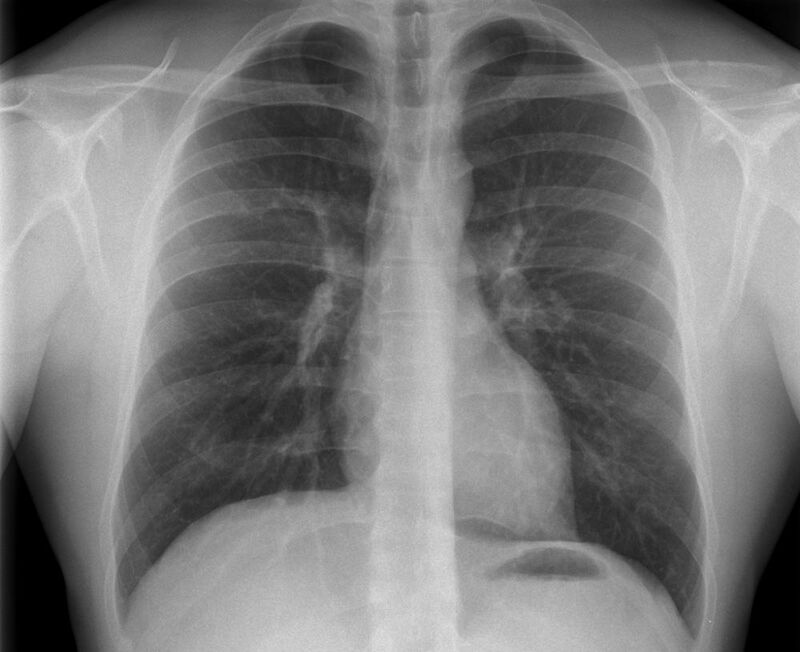

Röntgen Lunge

Röntgenaufnahme des Thorax

• Entzündungsdiagnostik (Pneumonie, gehäufte Bronchitis)

• Pleuraerguss

• Tumorverdacht

• Lungenemphysem

• Herzinsuffizienz

• Therapiekontrolle